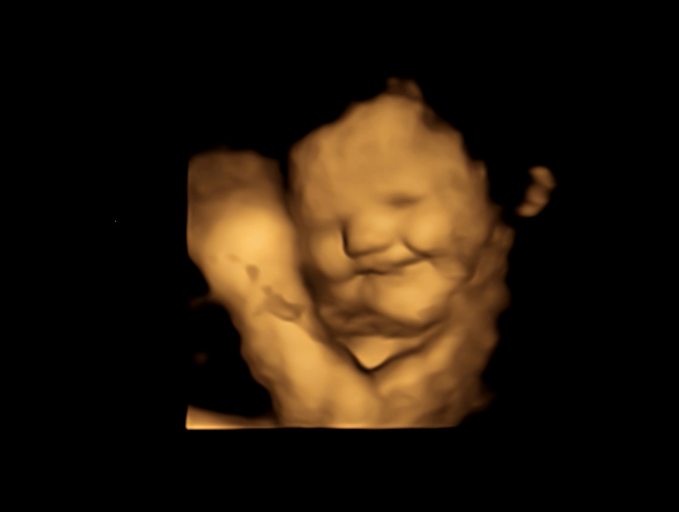

Kale no: Babies in womb indicate vegetable preferences with facial cues, study says